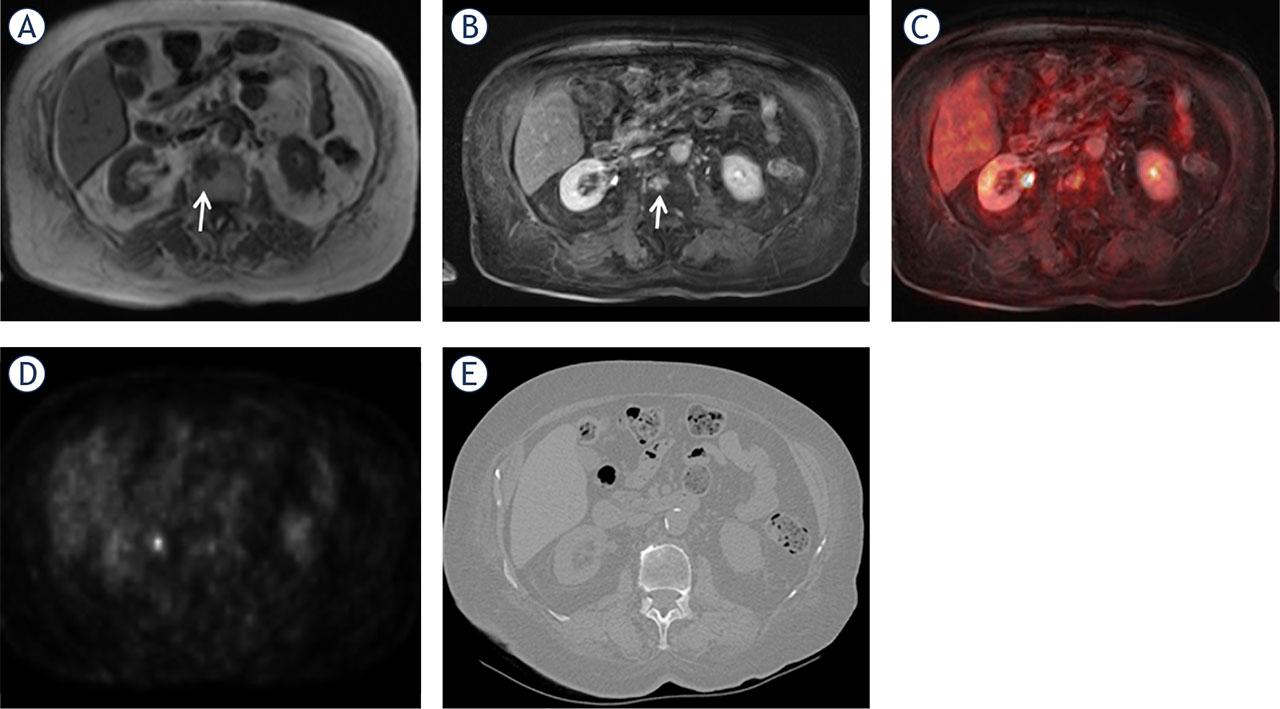

FIGURE 1.